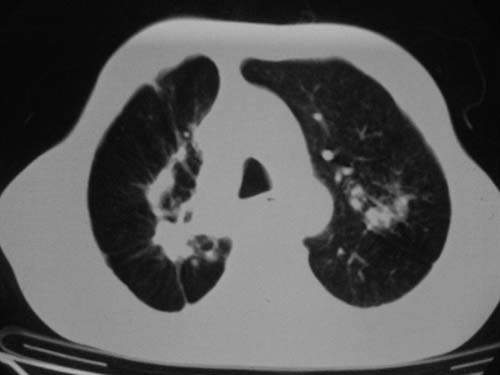

男性,45岁,胸疼,低热,抗炎治疗后症状缓解拍片检查发现左上肺有高密度灶,考虑结核,做ct示条件有限采集了部分图像,图像质量差请谅解

病灶有分叶,毛刺,考虑肺癌可能性大,建议穿刺。

病灶有分叶 毛刺 左侧叶裂上移 考虑肺癌可能性大 建议穿刺

右上肺结核,左上肺周围型肺癌可能性大

考虑两肺上叶继发性肺结核;肺气肿(多发肺大泡)。

团块状病灶,病灶周围长毛刺及灶周肺气肿。